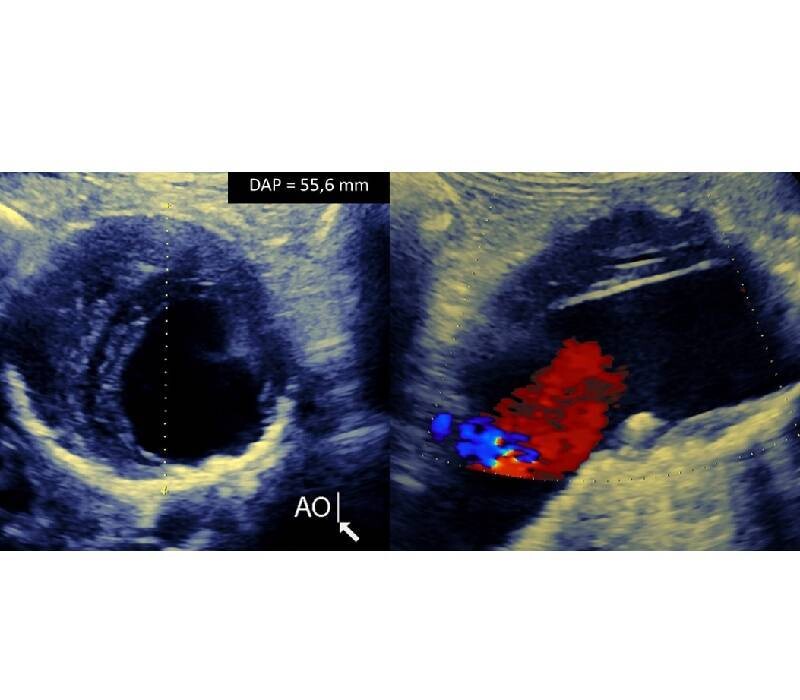

Quels tests sont utilisés pour dépister la sténose de l'artère carotide ?

Bien que le dépistage de la sténose de l'artère carotide chez les patients asymptomatiques ne soit pas recommandé, il existe 3 types d'imagerie qui peuvent être utilisés pour rechercher une sténose de l'artère carotide : l'échographie carotidienne, l'angiographie par résonance magnétique ou l'angiographie par tomodensitométrie.